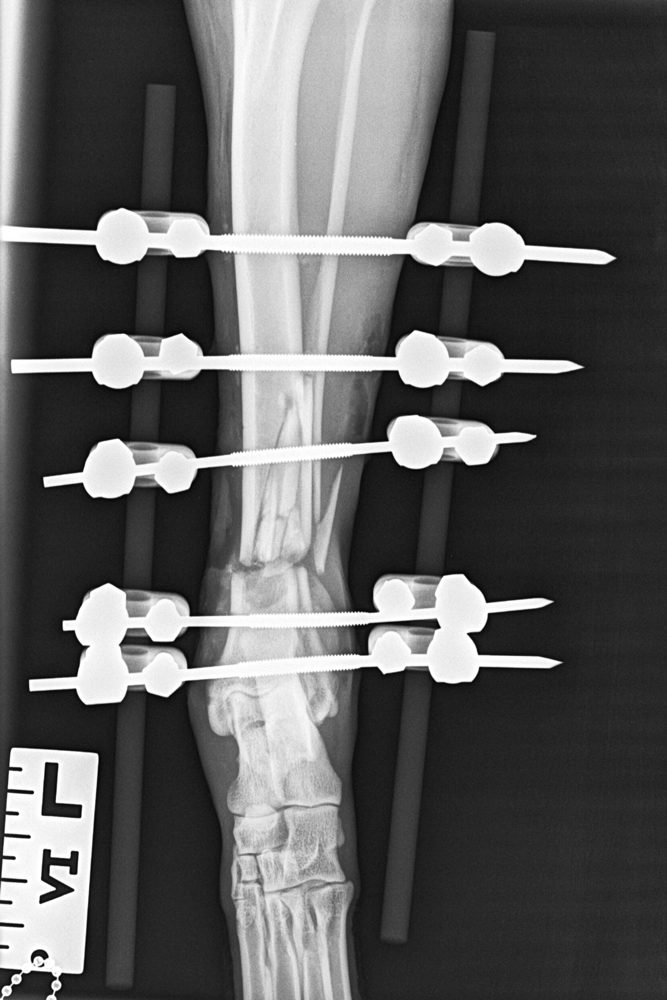

Fracture Repair

Many fractures can be managed by either internal (plate/ rod) fixation or external fixation (ESF). An estimate can be provided after review of radiographs, please include a size calibrated marker on films.